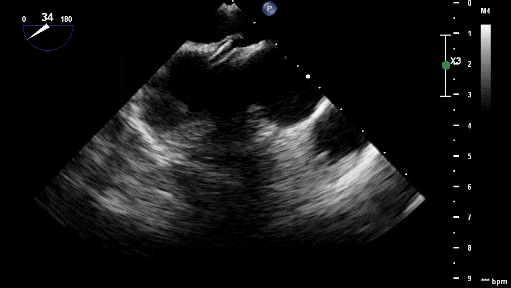

沿加硬導絲將9F輸送鞘送至左心房,退出導絲及輸送鞘內芯后,在超聲引導下送入1824PFO封堵器進行封堵。先釋放左盤面,整體回撤,緊貼房間隔,后釋放右盤面,進行推拉試驗,超聲在主動脈短軸切面、四腔心切面確認封堵器對二尖瓣等周圍組織無影響,位置及形態良好后釋放封堵器。撤出長鞘、縫合穿刺點后壓迫止血,加壓繃帶包扎,手術結束。

釋放左盤面及腰部

釋放右盤面

超聲觀察對周圍組織無影響

封堵器釋放后成型良好,無殘余分流